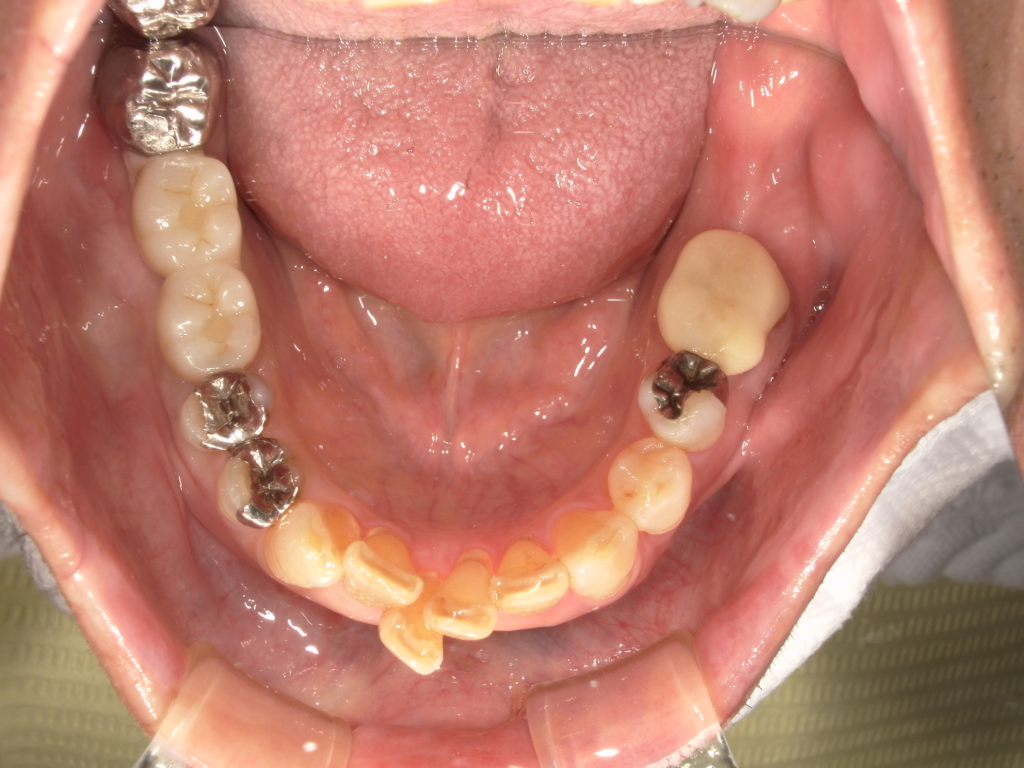

Y様インプラント実例 #44

左の上下の奥歯をインプラントで治療しています。

左下の奥歯は歯を抜くのと同時にインプラントの埋め込みを行っています。

被せものは上下、セラミックスで作っています。

治療前

治療後